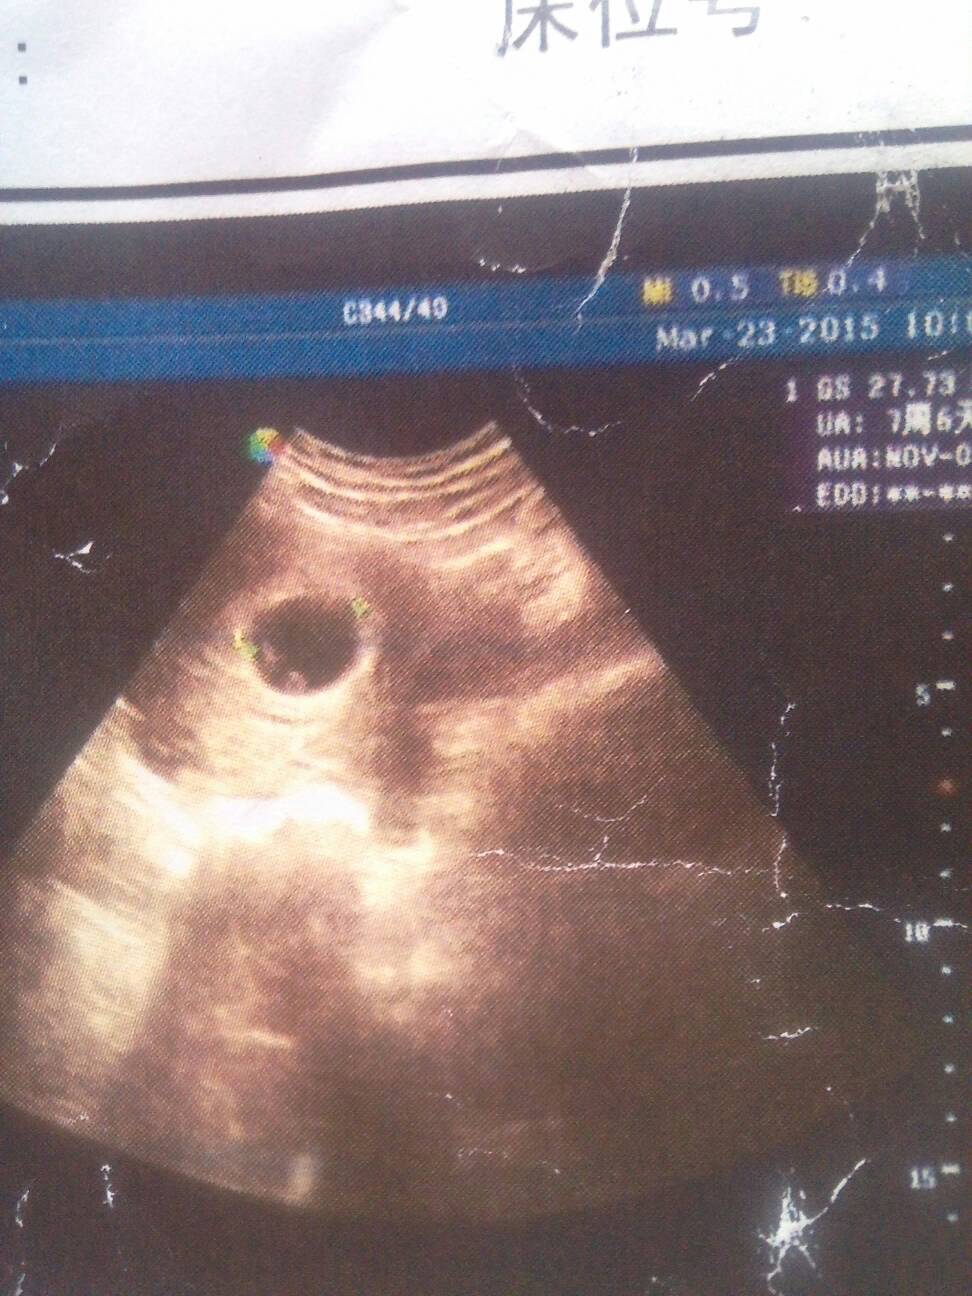

总感觉自己怀双胞胎了,严重吃不下饭 恶心也很严重,做梦梦见的东西都是两个,这是前几天的彩超单帮忙看

总感觉自己怀双胞胎了,严重吃不下饭。恶心也很严重,做梦梦见的东西都是两个,这是前几天的彩超单帮忙看看